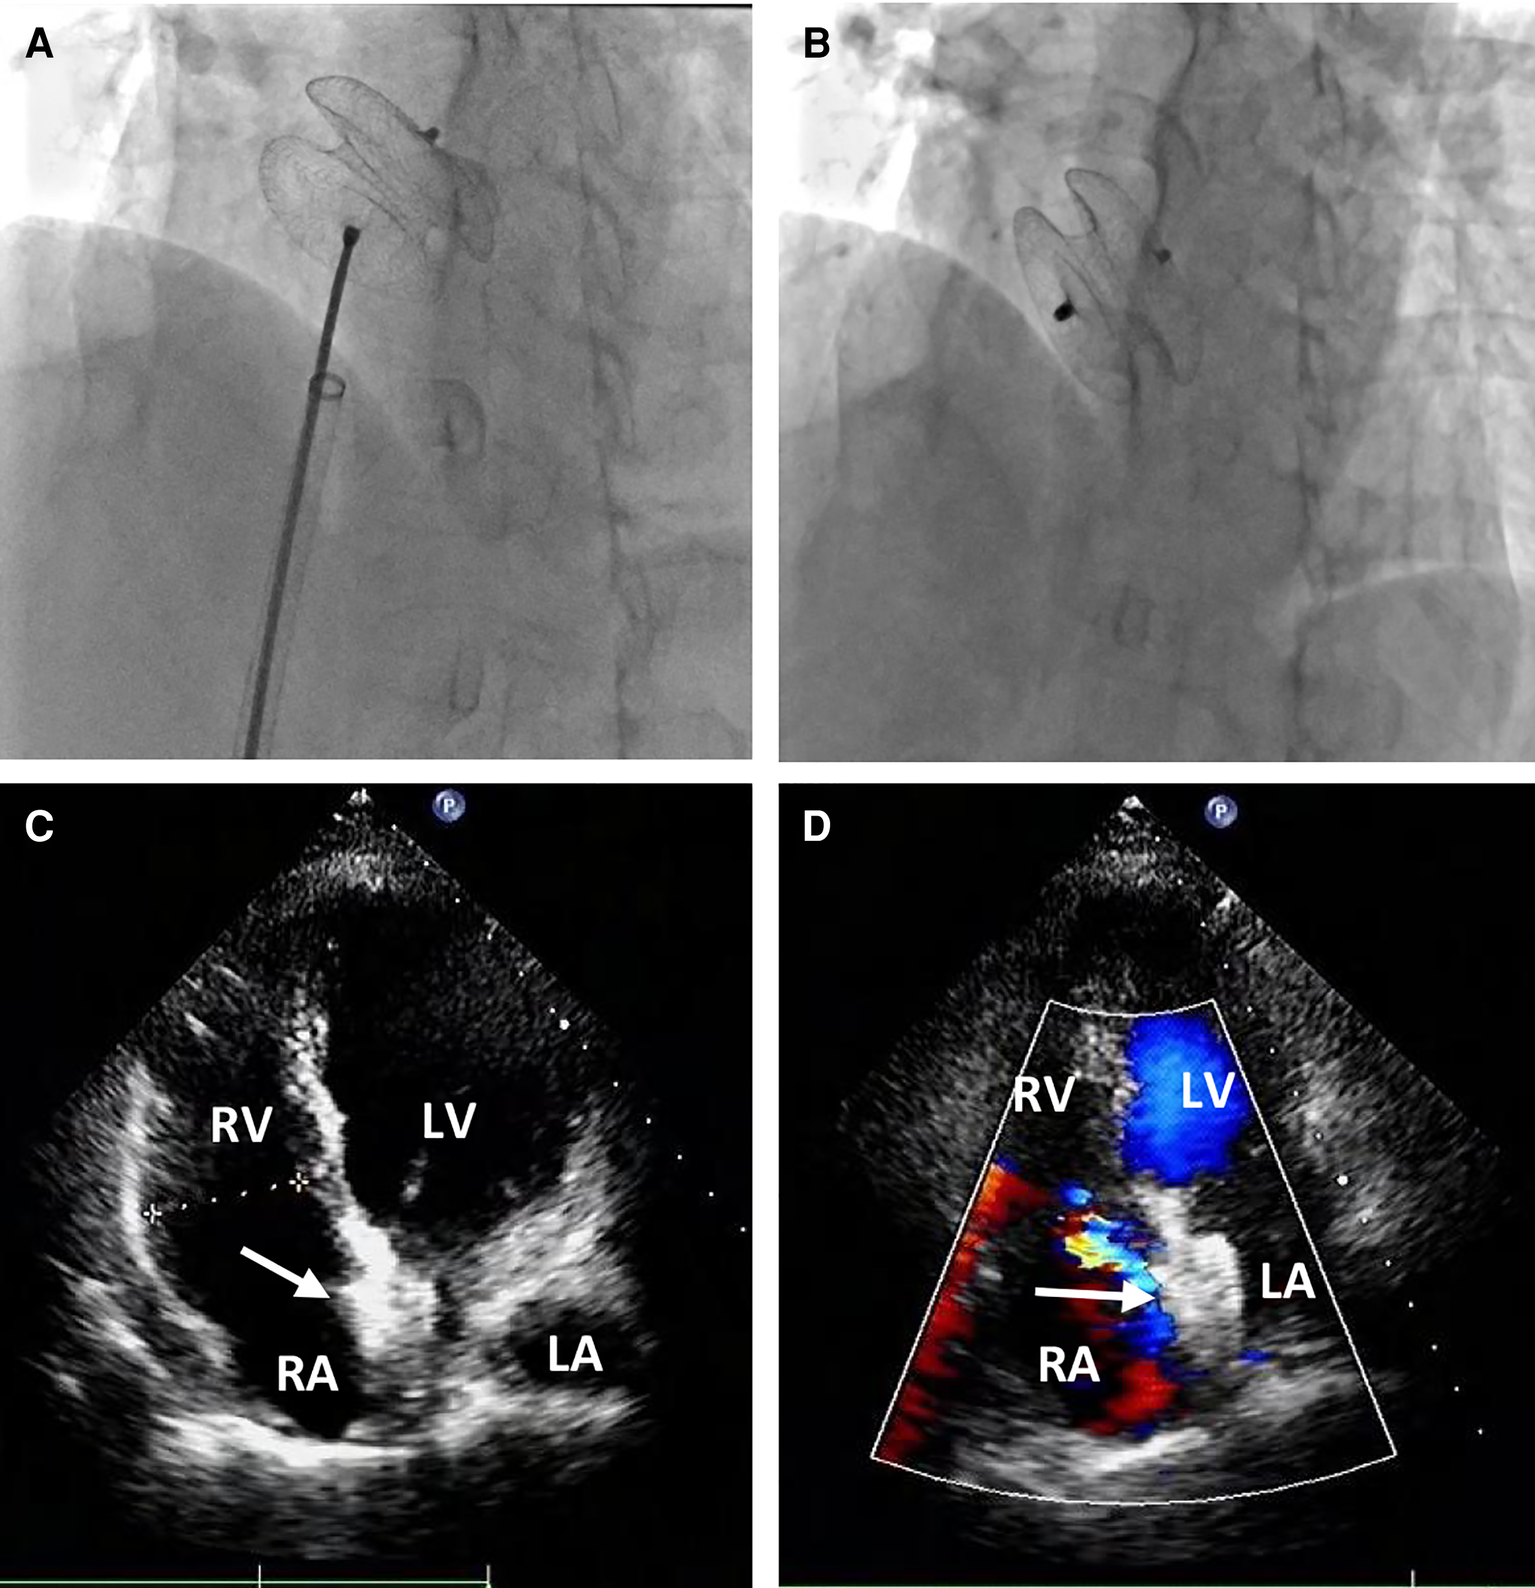

Figure 4

Percutaneous redeployment of the ASO device. Fluoroscopy revealed the 26 mm occluder was sent into the left atrium and the two sides of the occluder were successfully deployed on both sides of the defect (A); the position and shape of the redeployed occluder (white arrow) were found to be optimum, and no residual shunt (B) The occluder was located in the middle of the atrial septum (C) with no residual shunt (D) during the follow-up period.

Following the procedure, the patient was hospitalized in the cardiac care unit for approximately nine days due to hypoxic-ischemic encephalopathy (HIE) and acute cerebral infarction. On the first postoperative day, the patient experienced intermittent convulsions under moderate intravenous sedation. Immediate head CT revealed significant swelling of the brain tissue in the right frontal, parietal, and occipital lobes, accompanied by shallow brain sulci and blurred boundaries between gray and white matter. The neurologist attributed these findings to HIE resulting from the cardiac arrest and initiated mild hypothermia therapy and cranial pressure reduction. On the third postoperative day, the patient no longer experienced convulsions but developed fatigue and reduced skin sensation in the left upper limb. A subsequent head CT scan revealed an acute and substantial area of cerebral infarction in the left cerebellar hemisphere, with a reduction in the swelling of the right frontal, parietal, and occipital lobes. The neurologists determined that thrombolytic therapy was unnecessary and prescribed medication to reduce cranial pressure and improve cerebral circulation. At discharge, on the ninth postoperative day, the patient exhibited sequelae of left upper limb dysfunction and was subsequently transferred to a local hospital for further treatment. During one month of clinical follow-up, the patient did not experience any cardiac symptoms or events, and transthoracic echocardiography confirmed the appropriate position of the occluder in the middle of the atrial septum, with no residual shunt (Figures 4C,D).